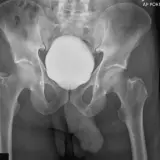

Over 2,100 interactive radiology cases, curated by radiologists for your level of training. Scroll, window, and view cases full screen โ€” just like on PACS. Click linked findings in each writeup to jump straight to them on the image. Cases include sample reports, a focused discussion section, original illustrations, and videos.

PACS์—์„œ ๊ธฐ๋Œ€ํ•  ์ˆ˜ ์žˆ๋Š” ๋ชจ๋“  ๋„๊ตฌ๋ฅผ ๊ฐ–์ถ˜ ์™„์ „ํ•œ ์ธํ„ฐ๋ž™ํ‹ฐ๋ธŒ ์ฆ๋ก€ — ์Šคํฌ๋กค, ์œˆ๋„์šฐ ์กฐ์ ˆ, ํ™•๋Œ€/์ถ•์†Œ, ํŒจ๋‹, ๊ณ„์ธก, ROI, ์ „์ฒด ํ™”๋ฉด ๋ชจ๋“œ๊นŒ์ง€ ์ง€์›ํ•ฉ๋‹ˆ๋‹ค.

์‹ค์ œ PACS ์›Œํฌ์Šคํ…Œ์ด์…˜์ฒ˜๋Ÿผ ์Šคํฌ๋กค, ํŒจ๋‹, ์œˆ๋„์šฐ ์กฐ์ ˆ, ํ™•๋Œ€/์ถ•์†Œ๊ฐ€ ๊ฐ€๋Šฅํ•ฉ๋‹ˆ๋‹ค